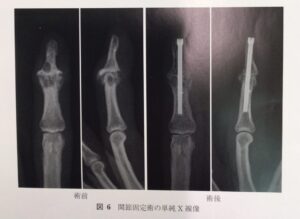

●手術療法